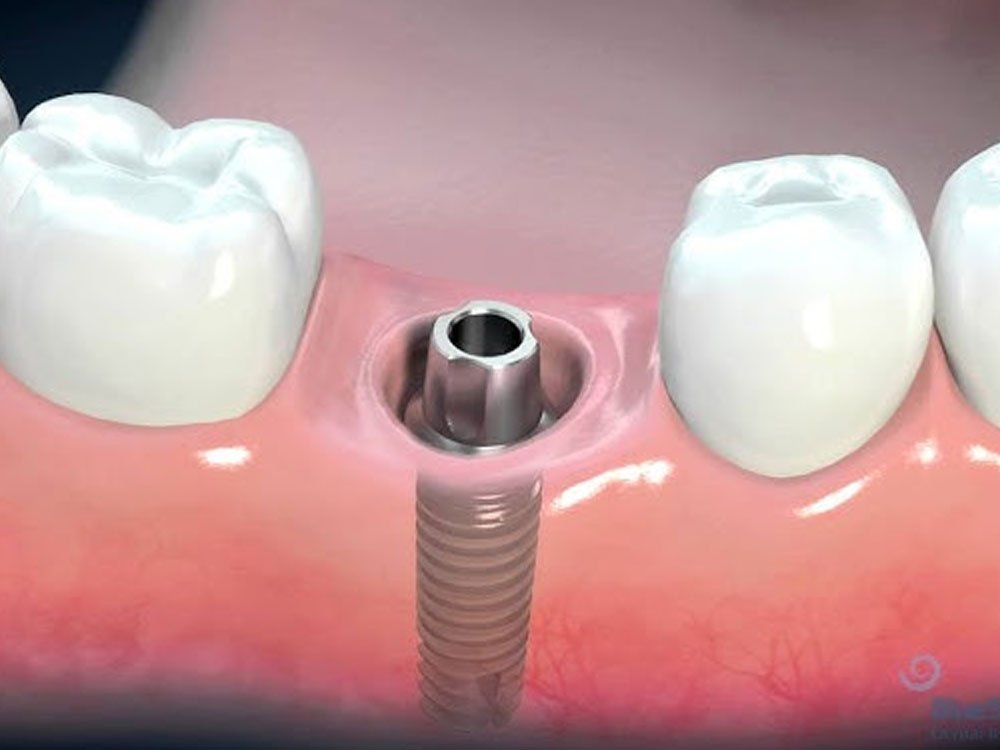

Tooth Replacement or Repair

We restore missing or damaged teeth with dental implants, bridges, or crowns. For patients with severe enamel wear, custom-made crowns or veneers are used to rebuild and protect the natural structure of the teeth.